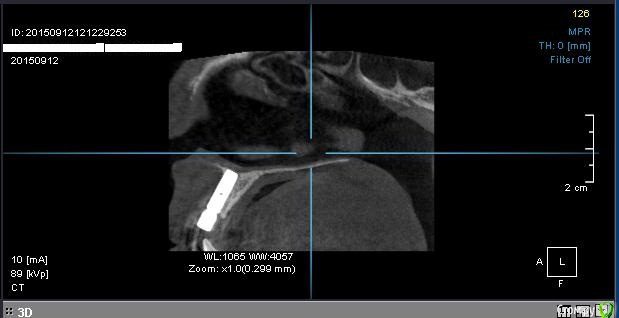

Ната-ли Опубликовано 16 сентября, 2015 Поделиться Опубликовано 16 сентября, 2015 Всем удачного дня!Совсем не знаю как мне быть ?! Просверлили нечаянно корень зуба, пришлось ставить имплант Astra Tech. Имплант стоит уже год. Болел пол года при эмоциональных , физических, психологических нагрузках ))) Имплан мой очень не любил спорт и горячий душ))) Но если просто лежать на диванчике, то имплант чувствовал себя прекрасно. Сумомед и кетанов стали моими неразлучными друзьями.) Кстати, нос тоже болел...наверное и нос как-то нечаянно задели имплантом))) Сейчас вроде по-легче.... Сделала снимок импланта в 3д. Когда расшифровали, я была в полном стрессе... Всё содержимое снимка, с моим вращающем черепом загрузить не получается...вот сделала скрин...(вид с боку)Имплант на 11-ом зубе , впереди держится только за слизистую, судя по снимку кости нет ...куда делась не знаю...то ли ушла куда-то, то ли так имплант вкрутили ...мимо кости???Выпиливать имплант не хочется....я же ещё часть кости потеряю ? Имплант беспокоит иногда (ноет, пульсирует), но я уже привыкла. Десна ушла вверх, может пластику десны сделать? (Хотя ни у кого из моих знакомых ни чего не получилось, слизистая, взятая с нёба , отваливалась вместе с нитками.Десна становилась ещё хуже и выше.)Не думаю, что "нарощенная" десна укрепит имплант ))),... но будет по-эстетичнее какое-то время...но потом десна вероятно снова поднимется, держаться-то ей не на чем )))Короче, что делать с десной не знаю...ПО поводу импланта ??? Думаю поставить пока коронку и посмотреть что будет дальше ? Я передними зубами есть ни чего не буду ))) просто для красоты хотя бы))) И буду ждать когда имплант сам выкрутиться ))) Или как ??? Ссылка на комментарий